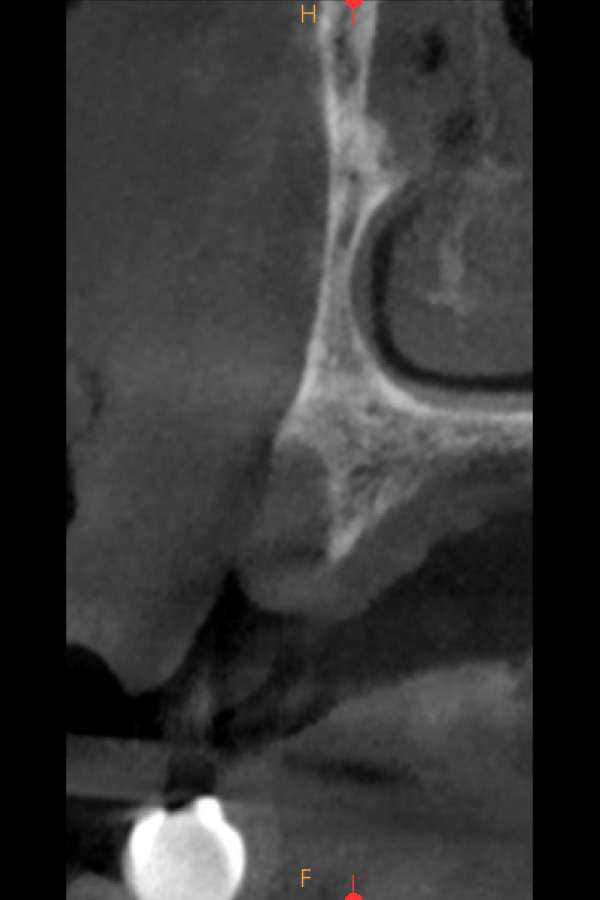

Figura 3, 4 y 5. Imágenes del CBCT en que se aprecia la poca disponibilidad ósea en sentido vestíbulo-palatino para la colocación de implantes dentales.